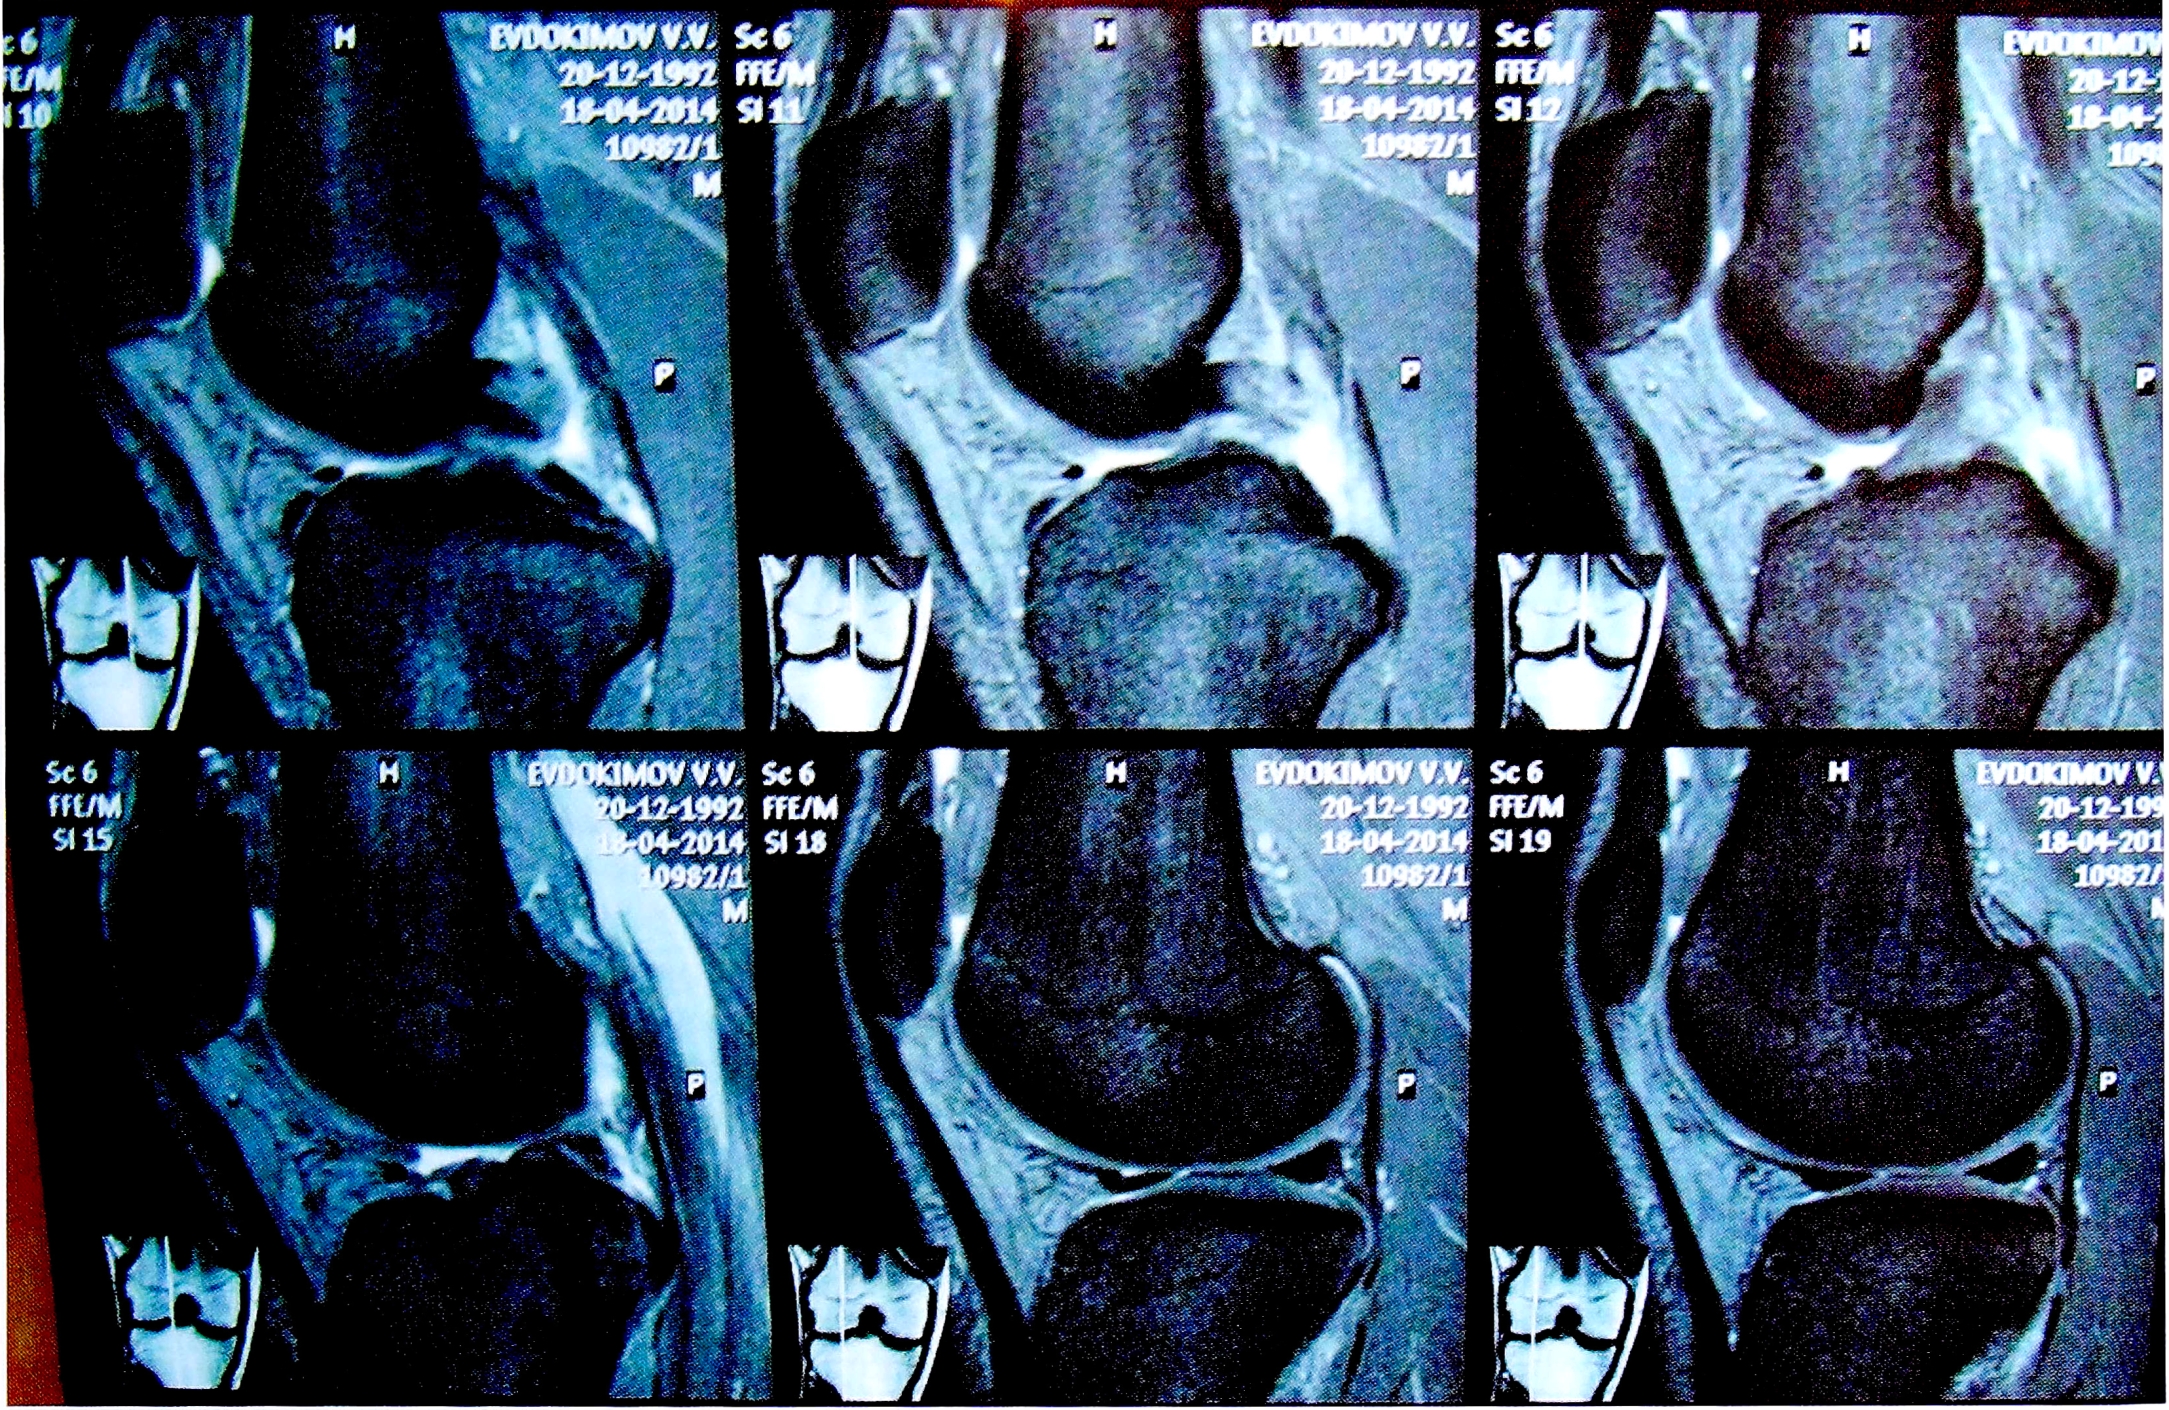

Перед операцией всем пациентам были выполнены МРТ коленного сустава (рис. 1) и рентгенография под нагрузкой (рис. 2). Результаты клинического осмотра, рентгенологических и MPT-исследований фиксировались согласно протоколу IKDC 2000. Для функциональной оценки коленного сустава были использованы опросники IKDC и Lisholm-Gillqist. Болевой синдром оценивался по визуальной аналоговой шкале (VAS).

Рис. 1. MPT-картина разрыва ПКС и ЗКС.

Fig. 1. MRI of PCL and ACL tears.